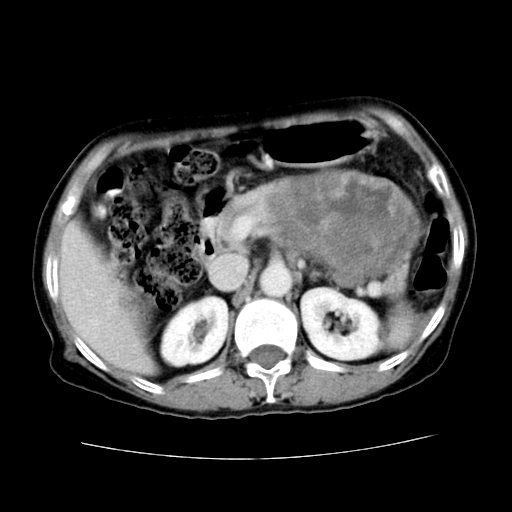

女性,72岁。

主诉中上腹部疼痛不适1年余。

胰腺尾部不规则巨大略低密度肿块,界限清楚,内密度不均,增强动脉期不均匀强化,门脉期明显退减并低于胰腺密度,肿瘤包埋于脾血管。多考虑;来源于胰腺尾部的“胰腺癌”。

该例有几个特点需注意:

1.肿瘤大而边界清

2.内部有钙化

3.强化时间较长

4.这么大的肿瘤对周围的血管无侵犯

以上几条均与胰腺癌不符

故考虑:胰岛细胞癌

1、这个病例确实有点难。影像主要显示胰腺体尾部占位,我们当初也是诊断胰体尾部囊腺癌可能性大,而且读片会上也很多人这么诊断的。

2、手术所见:打开腹腔发现胃与胰腺体尾部可见肿块,大小约10×8×11cm,质硬,不可推动,周围血供丰富。术中诊断:胃肿瘤侵及胰腺体尾部。

3、病理号:091860 2009年4月2日

1)、胃小弯侧胃肠间质瘤(考虑恶性),瘤体大小13.5×7×6.5cm,上下切缘阴性。

2)、胃小弯1只、幽门下2只淋巴结慢性炎。免疫组化:cd117(+)、cd34(+)、sma(+)、desmin(-)、s-100(-)、ki-67<10%(+).

4、这个肿瘤太大了,而且密度不均性强化,从这点我们应该不能单纯诊断胰腺癌,而应想到目前流行的胃肠道间质瘤。这个肿瘤主要发生于胃壁浆膜层,所以显示与胃壁关系不是很紧密,故而大多认为是胰腺癌。